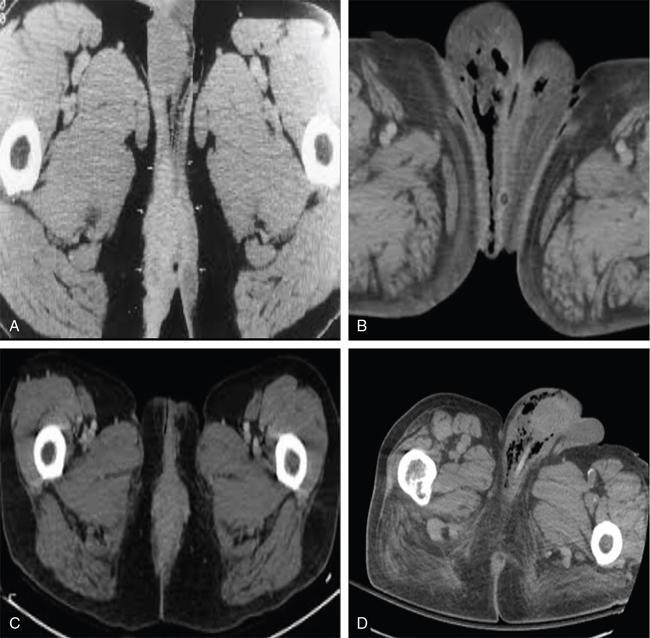

Kingston Vijay, Jansi Vinod, Sivakumar FOURNIER GANGRENE (NECROTIZING FASCIITIS): AN INFREQUENT TISSUE EATING DISEASE Fournier’s gangrene (FG): An awful infection of the visible genital region that causes grievous pain in the perineal area, which progresses from erythema to necrosis of tissue. FG is an acute dreadful urologic emergency, which has a high mortality rate of 15%–50%. It is a swiftly advancing, polymicrobial necrotizing fasciitis of the perineal, perianal and genital regions, which leads to reduced local blood supply causing vascular thrombosis in the skin and subcutaneous tissues. Subsequent spread of bacterial infection ensues with transfascial spread leading to development of gangrene of the overlying tissues. Fascial necrosis occurs at a rate of 2–3 cm/hr, making early diagnosis pivotal. Early diagnosis is essential and warrants surgical debridement and antagonistic triple antibiotic therapy. Computed tomography (CT) helps to confirm the diagnosis in clinically doubtful cases. In addition, radiography or ultrasound (US) can denote certain useful findings of FG, but CT has greater specificity for the diagnosis and displays the disease extent. Every radiologist must fathom out the imaging features of FG to document accurate diagnosis and urgent surgical treatment. FG is an acute terrible necrotic infection of the scrotum, penis and perineum. It is manifested as scrotal pain and redness with expeditious progression to gangrene and sloughing of tissue. FG is habitually secondary to perirectal or periurethral infections associated with local trauma, lower urinary infection and other operative procedures. The primary focus is located in the genitourinary tract, lower gastrointestinal tract and in the skin. FG is caused by both aerobic and anaerobic bacteria. It can eventually lead to multiple organ dysfunction syndrome (MODS) and death in severe cases. Owing to the dreadful complications, it is crucial to diagnose FG as quickly as possible. In spite of the antibiotics and surgical debridement, the death rate of FG remains high. It was first reported by Jean Alfred Fournier, who was a French professor of dermatology at St. Louis venereal hospital, the University of Paris in 1883. He observed a necrotizing gangrenous infection of male genitalia in young healthy males without any apparent source. The perineum is the area referring to the shallow internal compartment and external surface of the body (Fig. 11.11.1.1). The compartmental area of perineum is seen inferior to the pelvic outlet and is divided from the main pelvic cavity by the pelvic diaphragm. This pelvic diaphragm holds up the urogenital and gastrointestinal systems and plays an important role in defecation, micturition, sexual intercourse and labour. When viewed in subject with abducted thighs, the perineum resembles a diamond-shaped area that is bounded by the mons pubis anteriorly, medial aspect of the thighs laterally and the gluteal folds and upper end of natal cleft posteriorly and following osseofibrous boundaries: An imaginary transverse line connecting the anterior ends of the ischial tuberosities splits the perineum into two triangles: It is located in the rear half of the perineum. The sacrotuberous ligaments, the coccyx and an imaginary line connecting bilateral ischial tuberosities bound it. The major contents are: The main nerve of the perineum, the pudendal nerve is located in the anal triangle. The urogenital triangle is the front half of the perineum. It is bounded by pubic symphysis, ischiopubic rami, and an imaginary line between the two ischial tuberosities. Urogenital triangle has number of fascial layers and pouches and complex. Dissimilar to the anal triangle, the urogenital triangle has an extra layer of strong deep fascia, which is called as perineal membrane. The membrane has pouches on the superior as well as inferior surfaces (Fig. 11.11.1.3). The layers of the triangle (deep to superficial) (Fig. 11.11.1.4): Is located on the midpoint of theoretical transverse line joining the ischial tuberosities that is providing attachment to the perineal muscles. Perineal body lies deep to skin and subcutaneous tissue in the midline at the junction of anal and urogenital triangles. It is seen behind the vestibule of the vagina or bulb of the penis. Anus and anal canal are seen behind the perineal body. The perineal body is varying in size with little fat deep to the overlying skin (Fig. 11.11.1.6). All the perineal muscles converge in the perineal body and have three stratum. Superficial stratum includes bulbospongiosus, superficial transverse perenei muscles and superficial part of external anal sphincter. Intermediate stratum includes sphincter urethrae and deep transverse perenei muscle and deep part of the external anal sphincter. Deep stratum contains levator ani muscle. It is a triangle-shaped musculofascial diaphragm situated in anterior half of the perineum located in the region of the urogenital triangle filling space of pubic arch. It is pierced by urethra in both male and female and vagina in females. It holds the prostate gland and it constricts the vagina. It has: Infection of superficial perineal fascia (Colles’ fascia) may spread to the penis and scrotum across the Buck and Dartos’ fascia. Infection can spread into the anterior abdominal wall along the Scarpa’s fascia. Colles’ fascia limits progression of disease as it is attached to the perineal body and urogenital diaphragm posteriorly and to pubic rami laterally. Testis is rarely involved, as the testicular arteries originate directly from aorta. Well-advanced FG can extend from the fascial envelop of the genitalia throughout the perineum, across the torso and upper thighs. The superficial perineal space receives its blood supply from the internal pudendal artery, which is the branch of the internal iliac artery. Pudendal nerve and its branches are supplying the superficial perineal space. The posterior labial nerve, which is a branch of pudendal nerve has a medial and lateral branch and runs along the lateral part of the urethral triangle to supply the skin of the labia majora. The posterior scrotal nerve, which is branch of pudendal nerve has a medial and lateral branch and runs along the lateral part of the urethral triangle to innervate the skin of the scrotum. FG usually not only involves the corpora, urethra, testes, cord structures and deep muscular structures, but also the superficial and deep fascia as well as the skin. The infection spreads along the anatomical fascial planes. So knowing the routes of spread, familiarity with the perineal anatomy and its fascial planes is very important in understanding the potential pathways of disease spread. Thus if the Colles’ fascia is interrupted, then the infection can easily spread to the ischiorectal fossa and subsequently to buttocks and thighs. Urethral stricture Scrotal abscess Epididymo-orchitis Hydrocele Surgery/Aspiration Traumatic catheterization Urethral calculi Prostatic biopsy Vasectomy Perianal abscess Rectal biopsy Anal dilatation Haemorrhoidectomy Rectosigmoid malignancy Appendicitis Diverticulitis Strangulated inguinal hernia Infected Bartholin’s gland Vulval abscess Septic abortion Episiotomy wound Coital injury Genital mutilation In FG, rotting bacterial infection can cause microthrombosis of small subcutaneous vessels bringing about gangrene of the overlying skin. Cultures of FG wound often show poly microbial infections by aerobes and anaerobes, which include: Nonuniformity in clinical presentation. From subtle onset and slow progression to swift onset and fulminant course. Symptoms of FG include scrotal oedema, hyperemia, fever, pain, pruritus and crepitus. Crepitus is a common feature because of the presence of gas under the skin. Air in the soft tissues is produced by anaerobic bacteria and consists primarily of nitrogen, hydrogen, nitrous oxide and hydrogen sulphide. FG infection starts as cellulitis then necrotic patches start appearing over the skin and progress to extensive necrosis. Leucocytosis, anaemia, thrombocytopenia, dehydration, tachycardia, hypocalcaemia, and hyperglycaemia are the systemic manifestations of FG. FG can rapidly progress to septicaemia and multiple organ failure. Involvement of the testis is very rare, which suggests retroperitoneal origin or spread of infection. The diagnosis of FG is usually clinical. Imaging has an ancillary role. Radiologic evaluation is indicated when the diagnosis is not clearly established. The goals of radiologic evaluation are: Radiolucent soft tissue gas shadow may be seen over the scrotal or perineal region. The subcutaneous air pockets can enter from scrotum and perineum to the anterior abdominal wall, inguinal regions and thighs. Soft tissue air pocket visualized on X-ray of diabetic patients with FG in 100% of the cases, while physical examination can pick up scrotal wall air pockets only in 29% of the cases. High-resolution linear transducer (5–15 MHz) imaging of scrotum is a helpful tool in the diagnosis of FG prior to the clinical suspicious or physical examination of the disease. Ultrasound scan can show widespread abnormalities of scrotum such as scrotal wall oedema/cellulitis, testicular torsion, acute epididymo-orchitis, testicular trauma, necrotizing fasciitis and an obstructed inguinoscrotal hernia. Ultrasound can also display a thickened oedematous scrotal wall, air shadows within the scrotal wall, paratesticular fluid collection. Presence of subcutaneous air pockets in the scrotal wall with unhealthy echogenic white after shadows is the sonographic hallmark of FG. This distinct sonographic appearance of scrotal wall air shadows is due to fluid–air interface. Often the testis and epididymis are normal in size and echotexture because of different blood supply directly from abdominal aorta through testicular arteries. An obstructed inguinoscrotal hernia may show the presence of air shadows within the bowel loops or within the scrotal sac but not in scrotal wall layers. Many times ultrasound scan depicts the presence of air pockets in nearby subcutaneous soft tissues other than scrotal wall before physical examination does. Distribution of soft tissue air pocket may indicate the extent of the disease in multiple fascial planes. Scrotal wall emphysema may extend into the perineum, inguinal region and abdominal wall and occasionally into the thigh. Absence of scrotal wall emphysema dose not excludes the diagnosis of FG. CT is a very valuable tool in diagnosing and determining the extent of FG. Clear knowledge of the anatomy of perineal region and fascial planes, the extent of the disease can be established to a degree more specific than is possible with physical examination/sonography. CT is the modality of choice in FG. CT findings include: CT scan dominates in the detection of deep-seated perineal, pelvic and intraabdominal fluid collections, which is very important in the eradication of the disease. It also provides wide field of view of perineum, pelvis and proximal portion of the lower extremities. Retroperitoneal extension is also well demonstrated with CT. Extent into anal triangle and urogenital triangle can be clearly made out. CT screening of perineum and pelvis can frequently show the underlying cause of the FG such as urethral pathology, perianal abscess, fistulous tracts, incarcerated hernia and source of infection that may be from intraabdominal or deep pelvic process and helping to planning of surgical debridement and management. Posttreatment follow-up CT scan is very important in assessing for improvement or worsening of FG. CT is useful in deciding additional therapy or surgical excision. MRI scan of the pelvis and perineal region is used to assess the extent of FG along the tissue planes. MRI yields better soft tissue details than the CT scan (Fig. 11.11.1.8). STIR imaging displays the oedema/inflammation of skin, subcutaneous fat and inter muscular planes as hyperintense shadows. Air loculi present in interstices of scrotal wall appear as hypointensities. MRI scan clearly demonstrates the extension of FG inflammatory process into the inguinal canal, pelvic cavity and in ischiorectal fossa as bright hyperintense shadows. Prolonged time for MRI scan, patient monitoring difficulties, clinically unstable patients limit the practical usefulness of MRI scan. The mortality in FG is little high ranging from 3% to 45%. Factors associated with high mortality include: Early presentation in good functional status along with appropriate and timely treatment leads to a good outcome. FG wound extending more than 5% of the body surface area carries a poor prognosis. Abdominal wall or lower limb involvement has notable increase in mortality rate. Used for prognostication and predicting mortality probability in FG. This is a numerical score derived from a combination of nine physiological variables including temperature, respiratory rate, heart rate, creatinine, sodium, potassium, bicarbonate, white cell count and haematocrit. FGSI score more than 9 indicates 75% mortality probability while less than 9 indicates a 78% survival probability. FG is an infrequent but quickly growing disease that mostly affects men with certain comorbid risk factors. In spite of all advances in medical care, it still continuous to be a disease with high mortality. The early debridement of necrotic tissue is the paramount factor for survival. ABDOMINAL WALL HERNIA Hernia refers to the protrusion of a part or structure through the tissues normally containing it through either through stretching or opening in normal tissues. Hernia may be external/internal. Hernias are the frequent imaging findings in abdomen. Most are asymptomatic but chances of developing complications present like incarceration, strangulation and trauma are present, so often they are surgically repaired. Using linear 10 MHz transducer inguinal region is examined. In obese patients 7 MHz may be required. During Valsalva, manoeuvres characteristic movement of herniating tissues through the defect clinches the diagnosis. This dynamic imaging is the added advantage in ultrasound. If bowel is the content peristalsis noted. If fat is the content in the sac, it appears hyperechoic. BOX 11.11.2.1 CLASSIFICATION OF EXTERNAL HERNIA

CT scan